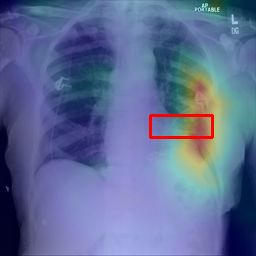

Deployments of artificial intelligence in medical diagnostics mandate not just accuracy and efficacy but also trust, emphasizing the need for explainability in machine decisions. The recent trend in automated medical image diagnostics leans towards the deployment of Transformer-based architectures, credited to their impressive capabilities. Since the self-attention feature of transformers contributes towards identifying crucial regions during the classification process, they enhance the trustability of the methods. However, the complex intricacies of these attention mechanisms may fall short of effectively pinpointing the regions of interest directly influencing AI decisions. Our research endeavors to innovate a unique attention block that underscores the correlation between 'regions' rather than 'pixels'. To address this challenge, we introduce an innovative system grounded in prototype learning, featuring an advanced self-attention mechanism that goes beyond conventional ad-hoc visual explanation techniques by offering comprehensible visual insights. A combined quantitative and qualitative methodological approach was used to demonstrate the effectiveness of the proposed method on the large-scale NIH chest X-ray dataset. Experimental results showed that our proposed method offers a promising direction for explainability, which can lead to the development of more trustable systems, which can facilitate easier and rapid adoption of such technology into routine clinics. The code is available at www.github.com/NUBagcilab/r2r_proto.